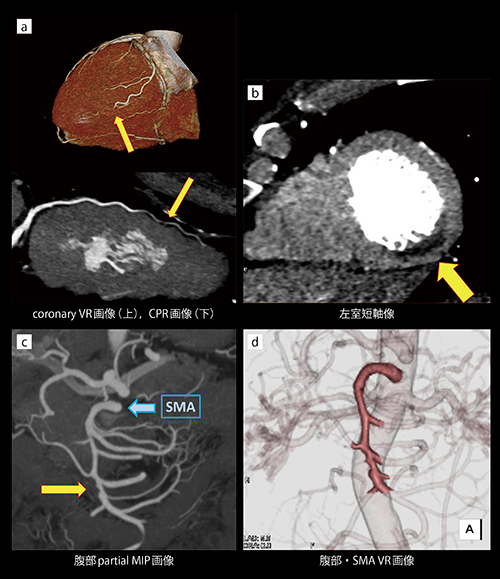

冠動脈解離とSMA解離を同時に描出できた緊急造影CT

末廣瑛里奈(神戸大学医学部附属病院医療技術部放射線部門)

【背 景】49歳,男性。突然の胸腹部痛および背部痛のため他院を受診し,心電図にて急性冠症候群が疑われ当院紹介となった。背部痛より大動脈解離も否定できなかったため,救急からまず胸腹部単純CTが依頼された。明らかな大動脈解離は認めなかったが,上腸間膜動脈(SMA)の内腔辺縁に高吸収域があり,周囲脂肪織の濃度上昇を伴うなど,SMA解離を疑う所見が見られた。そのため,冠動脈および大動脈の評価に加え,SMA精査のための造影CTも必要となり,緊急心臓CT検査が依頼された。

【所 見】冠動脈,SMAおよびその分枝は良好に描出され,画像再構成は容易であった。

心臓CTにおいては,左冠動脈回旋枝の#14末梢で,血管径の狭小化と造影効果の低下を認めた(a←)。

また,左室後側壁の心内膜側に造影効果の低下した所見を認め(b←), #14の灌流域として合致する領域であった。血管径が細く明らかな偽腔は確認できなかったが,冠動脈解離に伴う心内膜下梗塞と画像診断された。臨床的にも矛盾しない所見であった。

SMAには,起始直後より偽腔閉塞型解離を認めた。右結腸動脈分岐部にかけて真腔の狭窄が見られたが(c:SMAから→まで),末梢レベルでは閉塞など血流低下を示唆する所見は認めなかった。腹部はDual Energy CTによる平衡相を追加で撮影したが,やはり腹部臓器に虚血を疑う所見は見られなかった。また,大動脈には解離を疑う所見は認めなかった。

【訴求ポイント】冠動脈および大動脈,SMAは,いずれも動脈相の画像が求められた。ただ,心臓CT後に大動脈撮影を行うと動脈相のタイミングがずれ,また,検査を分けると造影剤量や被ばくの増加が懸念される。そのため,1回の撮影でいずれの動脈も評価するため,以下のように造影剤注入方法と撮影タイミングの工夫を行った。

(1) double level test injection法により,上行大動脈のピーク後,大腿動脈レベルに移動させることで,一度のtest injectionで上行大動脈と大腿動脈の造影剤ピーク時間を測定した。

(2) 上行大動脈および大腿動脈のピーク時間の差から,造影剤注入時間を最短時間になるよう決定した。造影剤注入レートは心臓CTと同様とした(22mgI/kg/s)。

(3) 撮影は心電図同期のChest PainモードのTurbo Flash Spiral撮影を用いた。拡張期での撮影とし,また,撮影タイミングは大腿動脈のピーク時間を参考に決定した。管電圧はCARE kVにより80kVが選択された。

緊急の心臓CT検査であったが,CTDIが2.9mGyという低被ばくで撮影でき,冠動脈,大動脈,SMA解離および血管狭窄範囲の評価を同時に行うことができた。